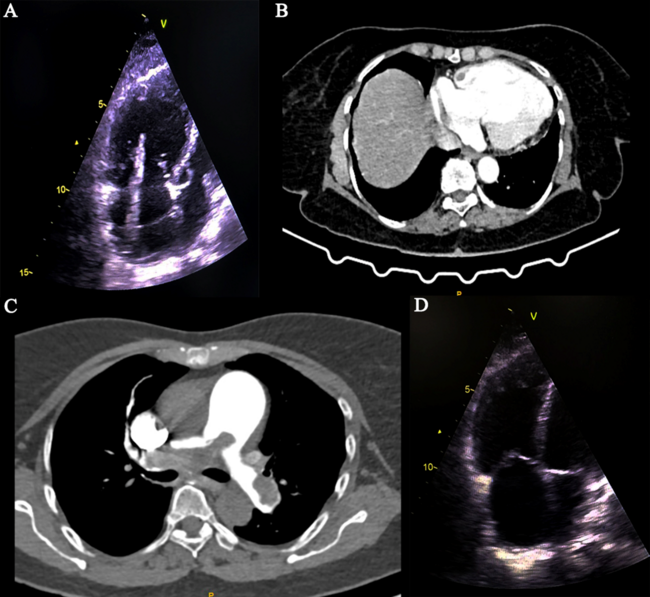

An elderly woman presented with worsening shortness of breath for a duration of 3 days. She had a history of provoked deep vein thrombosis of the right lower limb with a sub-massive pulmonary embolism (PE), for which she was on an oral anticoagulant for 2 years. Echocardiography showed a large, mobile, serpentine mass attached to the roof of the right atrium (RA) (Figure 1A, Video 1). Cardiac computed tomography (CT) characterized the mass as a thrombus and confirmed its attachment to the RA roof (Figure 1B). A massive PE involving the main pulmonary artery and both of its branches was also noted (Figure 1C). The PE Severity Index score was 163, which denoted high-risk PE, and systemic thrombolysis was done with tenecteplase. Subsequently, the thrombus in the right atrium completely resolved (Figure 1D, Video 2).